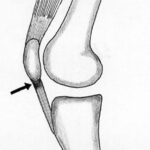

Lesões Meniscais do Joelho

Os meniscos são estruturas fibrocartilaginosas no joelho com diversas funções:

- Amortecimento

- Transmissão de forças

- Absorção de choque

- Estabilidade articular

- Lubrificação articular e nutrição

- Propriocepção

Pacientes com lesões meniscais frequentemente sentem dor na linha articular, associada a bloqueio articular e sensação de instabilidade (falseio).

Tratamento

A vascularização do tecido meniscal é crucial para o planejamento do tratamento. Apenas o terço periférico do menisco é vascularizado, o que significa que lesões fora dessa área têm baixo potencial de cicatrização. A preservação do tecido meniscal é fundamental para manter o equilíbrio articular. Mesmo em lesões com baixo potencial de cicatrização que exigem meniscectomia (remoção meniscal), busca-se remover a menor quantidade possível de tecido.